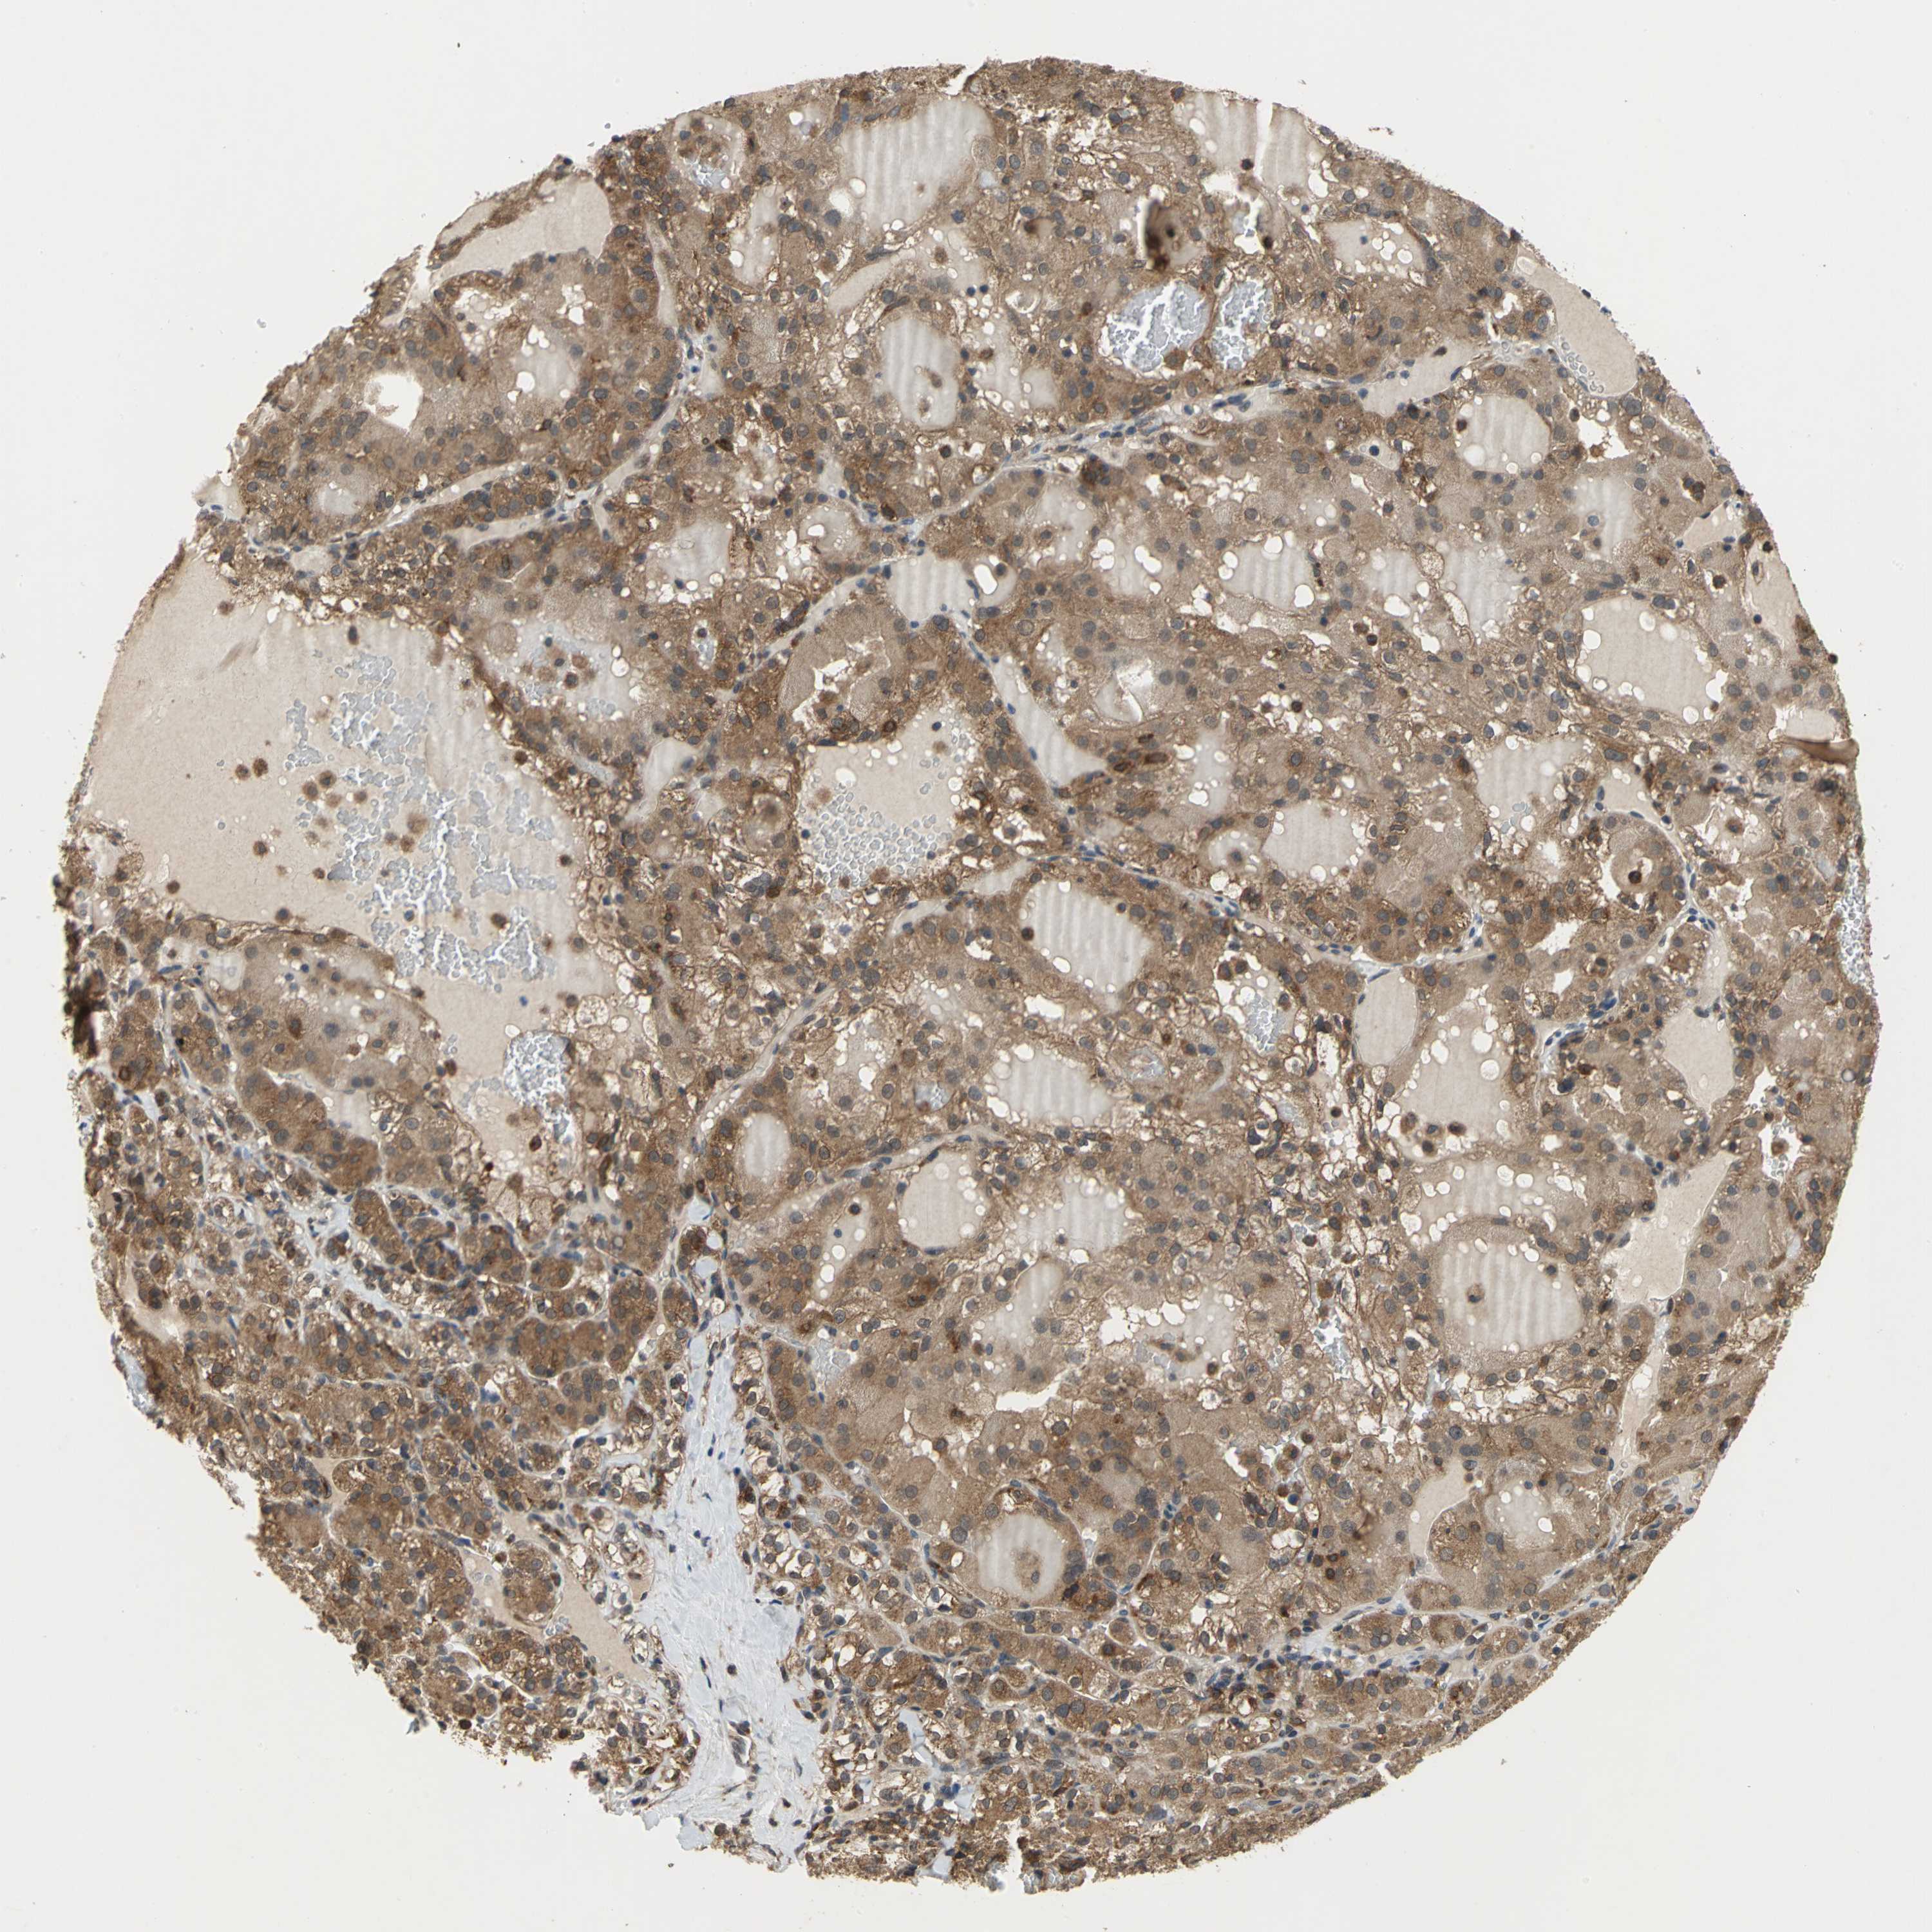

KIDNEY RENAL PAPILLARY CELL CARCINOMA (TCGA) - Interactive survival scatter ploti

The Survival Scatter plot shows the clinical status (i.e. dead or alive) for all individuals in the patient cohort, based on the same data that underlies the corresponding Kaplan-Meier plots. Patients that are alive at last time for follow-up are shown in blue and patients who have died during the study are shown in red.

The x-axis shows the expression levels (FPKM) of the investigated gene in the tumor tissue at the time of diagnosis. The y-axis shows the follow-up time after diagnosis (years). Both axes are complimented with kernel density curves demonstrating the data density over the axes. The top density plot shows the expression levels (FPKM) distribution among dead (red) and alive patients (blue). The right density plot shows the data density of the survived years of dead patients with high and low expression levels respectively, stratified using the cutoff indicated by the vertical dashed line through the Survival Scatter plot. This cutoff is automatically defined based on the FPKM cutoff that minimizes the p-score. The cutoff can be changed by dragging the vertical line or by entering a cutoff value in the square labeled "Current cut-off".

Under the Survival Scatter plot the p-score landscape (black curve; left axis) is shown together with dead median separation (red curve; right axis). Dead median separation is the difference in median mRNA expression between patients who have died with high and low expression, respectively. It is calculated as follows: median FPKM expression of dead patients with high expression - median FPKM expression of dead patients with low expression. This is intended to aid the user in visually exploring custom cutoffs and the associated p-scores and dead median separation.

Individual patient data is displayed and can be filtered by clicking on one or more of the category buttons on the top of the page. Categories describing expression level and patient information include: high, low, alive, dead, female, male and tumor stages. The scale of the x-axis can be toggled between linear and log-scale by clicking on the "x log" button. Mouse-over function shows TCGA ID, patient information and mRNA expression (FPKM) for each patient.

& Survival analysisi

Kaplan-Meier plots summarize results from analysis of correlation between mRNA expression level and patient survival. Patients were divided based on level of expression into one of the two groups "low" (under cut off) or "high" (over cut off). X-axis shows time for survival (years) and y-axis shows the probability of survival, where 1.0 corresponds to 100 percent.

NFKBIE is not prognostic in Kidney Renal Papillary Cell Carcinoma (TCGA)